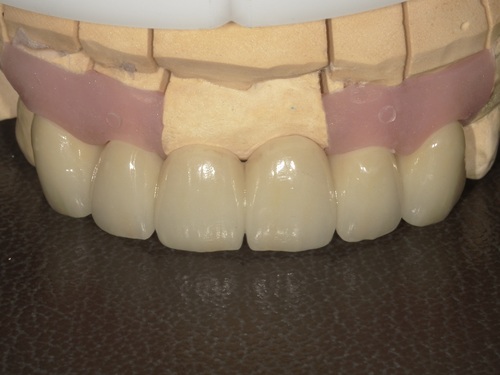

⑦セット

型取りから2週間ほどでジルコニアセラミックブリッジが完成してきました。

適合・色合い・噛み合わせに問題がないことを確認し、歯科用セメントでしっかりとセットしました。術前と比較して色も自然でとても美しい仕上がりかと思います。